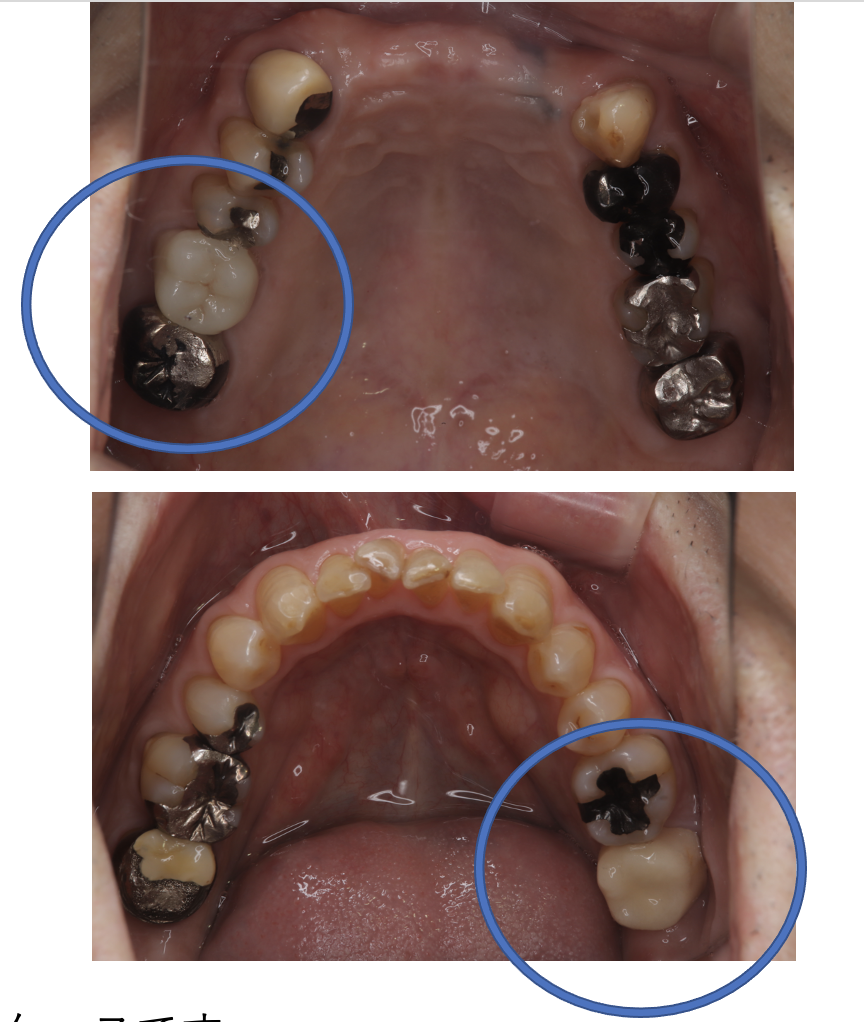

After

| 費用 | ¥89,000×2本=¥178,000 |

| 備考 | 院長より 銀歯の内部に虫歯が進行してしまっていたケースです。中を開けて見てみると、外から想像するよりもはるかに虫歯が広がってしまっていました。幸運にも神経を保存できたので、生きた臓器としてまだ使うことが可能です。残存歯質がかなり薄く弱くなってしまったので、ジルコニアで被せて守ってあげています。しっかりとした治療ができたので、まだまだ長く使っていけるでしょう。 |